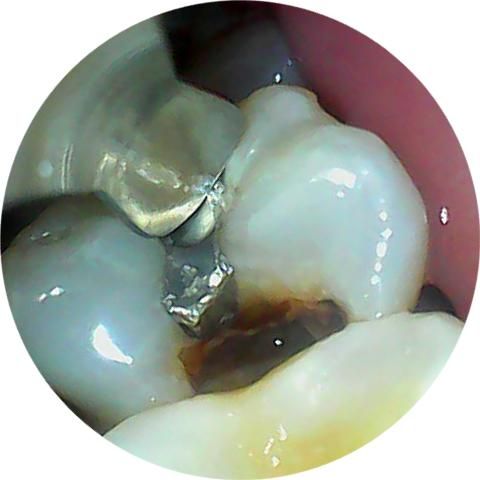

깨진 치아 지금이라도 치료 받아야되나여

며칠 아프다가 안 아파져서 잊고 살았는데, 어떤 상태인지 궁금해서 카메라로 찍어봤더니 요래 됐네요;;

1년 쯤 된 것 같은데 지금이라도 가야하나요?

이전의 아말감이 떨어져 나가고 내부로 충치가 생긴것으로 보입니다. 해당부위에는 이물질이 끼게 되어 충치가 더 생길수 있으며 치아가 파절될수 있기때문에 빠른시일내에 치료를 해주는것이 좋습니다.